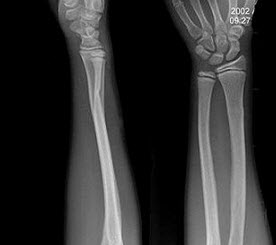

59、单项选择题

女,12岁,左前臂外翻畸形4年,摄片如图所示,最可能的诊断是()

A.奥利氏病

B.马德隆氏畸形

C.先天性干骺端发育不全

D.软骨发育不全

E.以上均不正确

60、单项选择题

女,27岁,跌倒后左手肿痛,结合X线图像,骨折类型是()

A.柯莱斯骨折

B.蒙泰贾骨折

C.加莱阿齐骨折

D.尺桡骨骨折

E.反柯莱斯骨折